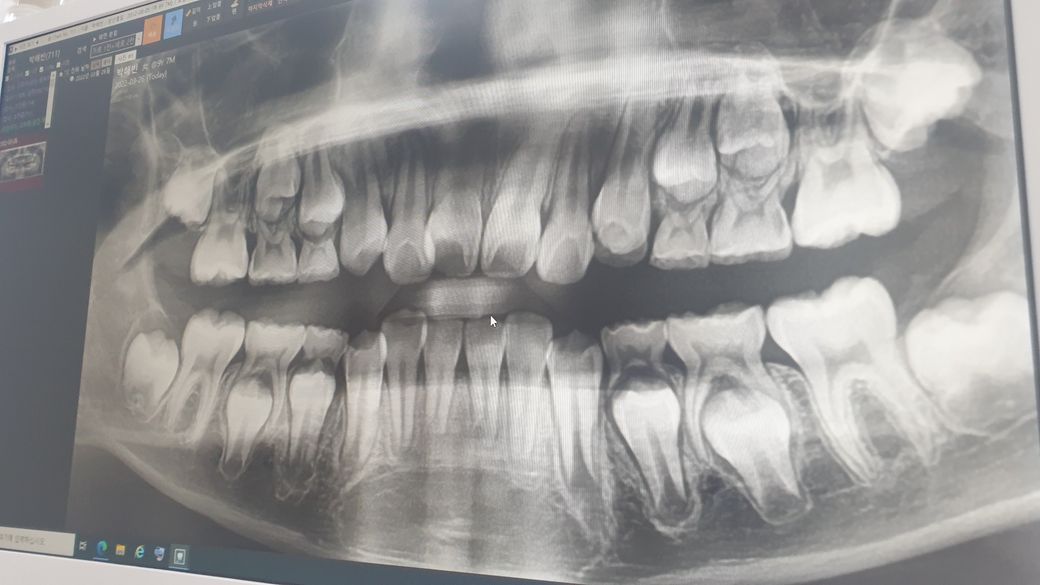

11살 딸아이 이빼러 갔는데 윗니 맨끝옆에 이가 충치가 생겼다고 하더라구요 맨끝에 이는 영구치이고 옆에 이는 유치여서 빠진다고 하는데ᆢ 사진봐서는 모르겠는데 충치 맞나요? 유치빠지고 충치치료 하는거 보다 지금상태에서 충치치료 하는게 맞는지 아하에 문의드립니다ᆢ

왼쪽과 오른쪽 유치 옆면에 충치가 있습니다.

빠지는 치아이지만 약 2년정도 사용할것 같으며 그전에 문제가 생길수 있으므로 치료를 해주는것이 맞는것 같습니다.

현재 사진 상으로는 정확히 알 수 없습니다. 충치라는 것이 깊지 않다면 방사선 사진 상에 잘 보이지 않습니다. 또한 방사선 사진은 2차원적으로 보이기 때문에 입체적으로 어떻게 위치하느냐에 따라 방사선 사진 상에 보이지 않을 수도 있습니다. 따라서 정확한 진단을 위해서는 지금과 같은 방사선 사진과 임상 사진이 동시에 필요합니다.

상악 5번째 치아 두군데 끝부분에 충치가 있는것으로 보입니다.

보통 저 치아들은 만 10~12세 때 빠지는 치아입니다만,

사진으로 보았을때 아직 뿌리가 좀 남아있어서 근시일 내에 빠질 것 같지는 않습니다. 따라서

충치치료를 해주시는것도 괜찮아보입니다.

파노라마 사진은 해상도가 낮기때문에 파노라마 사진만으로는 진단이 불가능합니다. 또한 치아우식증의 진단은 구강내 임상소견을 관찰하지 않고서는 확답하기 어렵습니다.

보통 11살이면 조만간 유치가 빠질 나이이긴합니다. 하지만, 유치의 뿌리가 아직 많이 남아 있어서 치료를 받으시는게 좋을것같습니다. 치아에 보시면 치아 뒤쪽으로 까맣게 보이는 부분이 충치입니다.

빨간색으로 동그라미친 부분이 다른 치아들보다 검은 부분이 있는 것을 보실 수 있으실 겁니다. 충치가 생겨서 치아가 이렇게 보이는 것 입니다. 치과용 파노라마 방사선 사진에서 저 정도로 뚜렷하게 보일 정도라면 충치가 있다고 판단할 수 있고 상당한 수준으로 진행했다고 생각할 수 있습니다.

물론, 질문자분이 카메라로 찍어서 가져오신 사진이라 약간의 왜곡은 있을 수 있으나 저정도 크기라면 충치가 높은 확률로 존재한다고 볼 수 있습니다.

우선 치료를 해야하는지 묻는다면 뒤에 존재하는 영구치(제1대구치; 첫번째 큰어금니)에 영향을 줄 수 있으니 치료하셔야 한다고 생각합니다.

사진으로만 봤을때는 해당치아의 충치가 깊습니다.

치료시 유치 신경치료를 하게될 가능성이 높고, 해당유치는 아직 빠지려면 1년이상 남았다고 판단되기 때문에 치료를 하는게 좋을 것으로 판단됩니다.